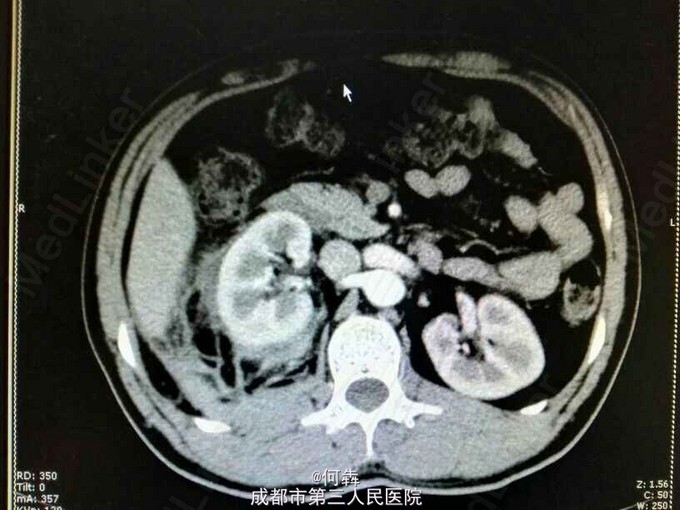

48岁男性,因“突发右腰痛1小时”入院,无血尿、外伤。既往无高血压、糖尿病。

右肾区扣痛阳性,余阴性。

右肾占位伴出血。入院后6天在全麻下行右肾部分切除术。术中冰冻及术后病检见图片